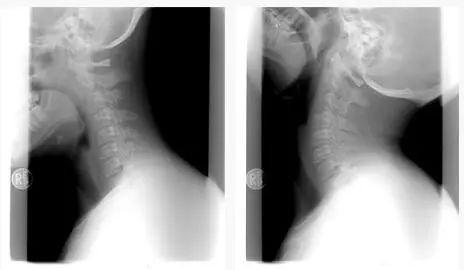

颈部三角区:常活动,防劳损

颈椎由颈椎骨组成,颈部金三角区是指颈后枕骨以下包括第一颈椎、第二颈椎的区域。

正常颈椎向前微凸,这样的弧度可增加颈椎弹性,使头部震动减缓。如果长期保持不良姿势,颈部的前凸就会逐渐变直,或转为后凸,会压迫正常工作的神经、血管,容易引发偏头痛、脑中风等。

高危因素

长时间低头、久坐,颈椎间盘突出。

粗暴按摩,颈部韧带受损。

枕头或枕头过高,颈部韧带劳损。

窝在沙发里,违背脊柱生理弧度。

趴桌子上补觉,颈椎变形。

专家建议

正确坐姿:双肩后展,脊柱正直,两足着地。

活动颈部: 每 一 两个小时左右就转动一次颈部,动作轻缓。

抬头远望:避免过长时间伏案或低头。

睡眠方式:睡眠选择合适的枕头。

防寒防湿:风寒潮湿会导致血管收缩,血流减慢。